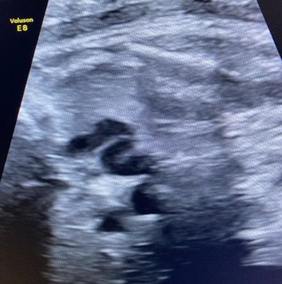

This concerns a 27 year old woman, feat 2, birth 0, abortion 1, with no significant medical history, currently at 35+5 weeks of gestation under obstetric care. She was referred to the fetal exploration unit due to suspicion of fetal cardiac malformation and tricuspid regurgitation. The fetal echocardiogram showed a structurally normal heart with mild tricuspid regurgitation, and no signs of heart failure were detected. Both ventricles exhibited good function. A dilated ductus arteriosus with an "S" shape measuring 10mm in length was observed, with a pulmonary end diameter of 3.2mm and an aortic origin diameter of 3mm (Figure 1 & 2). Ductal velocity was measured at 160cm/s. At the 37+6 weeks’ gestation evaluation, no significant changes were found compared to the previous fetal echocardiogram, with normal umbilical Doppler. The mother had a history of taking paracetamol at 29 weeks of gestation, every 8 hours for two days, due to a viral illness.

Figure 2 Image of ductus arteriosus arising from the aorta and with a 10mm tortuous course reaching the origin of the left pulmonary artery.